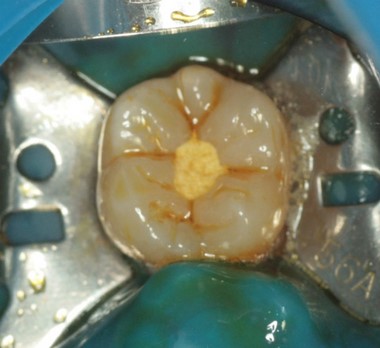

カリエス除去後まず、遠心をレジン充填(隔壁)。フロアブルレジンを使用。

? 削った時点で神経が見えており、出血がなく、神経が死んでいるのが確認できたので、次に根管治療を行います。

? この歯は樋状根でした。根管治療後、レジンコア+レジン充填にて修復を行いました。